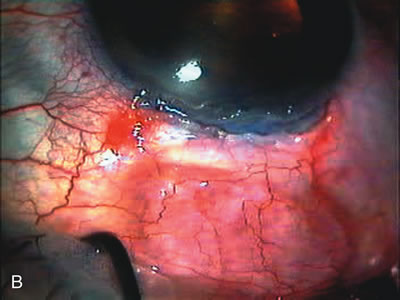

Cataract extraction by any technique performed in a patient with a pre-existing filter will have an effect on the previous filtering bleb.121–124 Bleb failure is more likely with ECCE compared with small-incision phacoemulsification.125 However, even patients undergoing topical anesthesia with clear corneal phacoemulsification and foldable IOL may experience bleb failure. One of three patients with a functioning filter and preoperative mean IOP of 12 mm Hg without antiglaucoma medications experiences bleb failure after lens extraction (Table 2). These patients require long-term drug therapy or bleb needling to control IOP. 126 Additional incisional glaucoma surgery may eventually be required in up to 10% of patients.127 Intraoperative iris manipulation may cause significant breakdown of the blood–aqueous barrier, resulting in inflammation that causes bleb failure. Even after uncomplicated clear corneal phacoemulsification, IOP may increase an average of 2 to 3 mm Hg due to bleb fibrosis.128 Approximately 20% of filtered patients require a long-term increase in glaucoma medications following uncomplicated clear corneal phacoemulsification with a foldable copolymer acrylic IOL129 (Fig. 3). In situations in which the bleb is not working at all, the eye will have a postoperative pressure spike that mimics that in the patient not having had a prior filtering procedure. In situations in which the bleb is marginal, the pressure spikes tend to be lower, and the final postoperative IOP tends to be around 50% higher than it was preoperatively. These patients require combined procedures in order to reestablish long-term filtration. In situations in which the bleb is very thin, polycystic, and associated with an IOP around 5 to 8 mm Hg on no antiglaucoma therapy; uncomplicated cataract extraction will have a minimal effect on the level of IOP. Patients with functioning glaucoma drainage implants usually have minimal long-term changes in IOP after uncomplicated cataract extraction.130

Fig. 3. Partial bleb failure following clear corneal phacoemulsification with foldable IOL. A. Preoperative bleb appearance prior to temporal lens extraction. Preoperative IOP was 12 mm Hg on no antiglaucoma medications. Time from 5-FU trabeculectomy surgery to lens extraction was one year. B. Bleb appearance 2 months after clear corneal cataract surgery with topical anesthesia. Following lens extraction, increased vascularity was noted along with decreased size of the filtering bleb. IOP increased to 20 mm Hg as early as 2 weeks after surgery, necessitating topical antiglaucoma therapy. C. High magnification view of bleb before lens extraction demonstrates diffuse pale bleb. D. High magnification view of bleb 2 months after surgery. There are vessels surrounding the nasal side of the bleb and the overall bleb size is smaller.